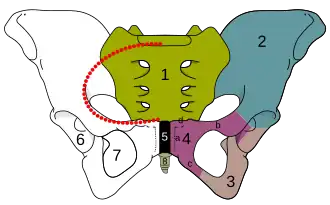

Pelvis.

Pelvis.